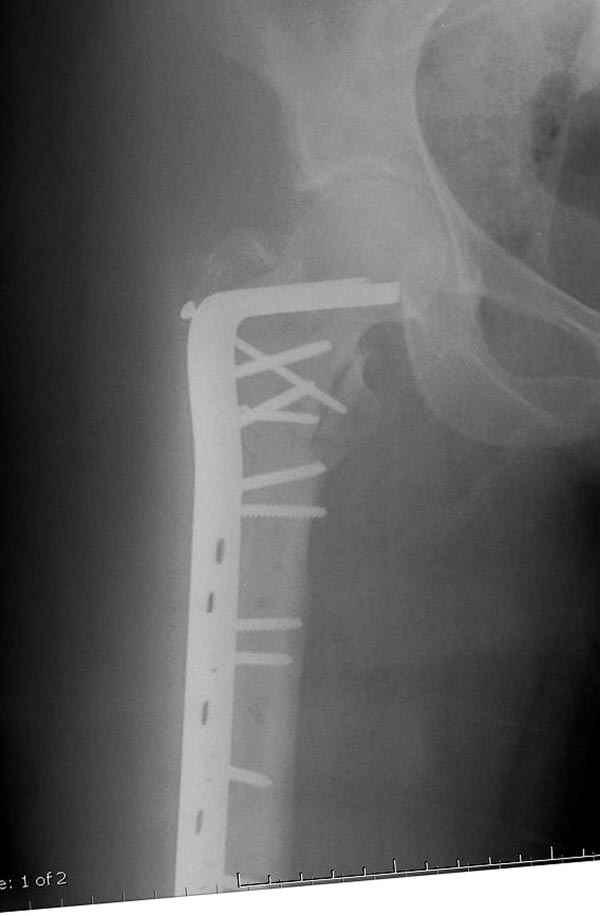

Другие случаи: применение Synthes TTFN (trochanteric titanium femoral nail) и Blade Plate (угловая пластина), так что много различных вариантов фиксации подобных переломов.